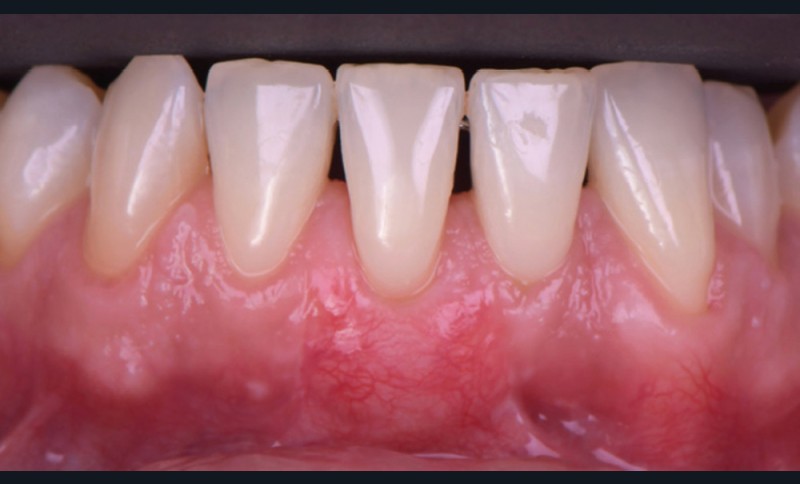

Le lambeau positionné coronairement associé à une greffe de conjonctif enfoui (fig. 1-4)

La stabilité du lambeau est primordiale dans la réussite de cette technique de recouvrement. En cas d’instabilité, même en l’absence d’erreurs techniques, l’analyse de certains facteurs liés au patient est indispensable. Afin de maintenir la stabilité du lambeau jusqu’à la dépose des points, le praticien doit veiller à l’adéquation du contrôle de plaque effectué par le patient, à l’absence de mastication impliquant la zone d’intervention, à la prévention de tout traumatisme ou de modifications des conditions locales par le patient.